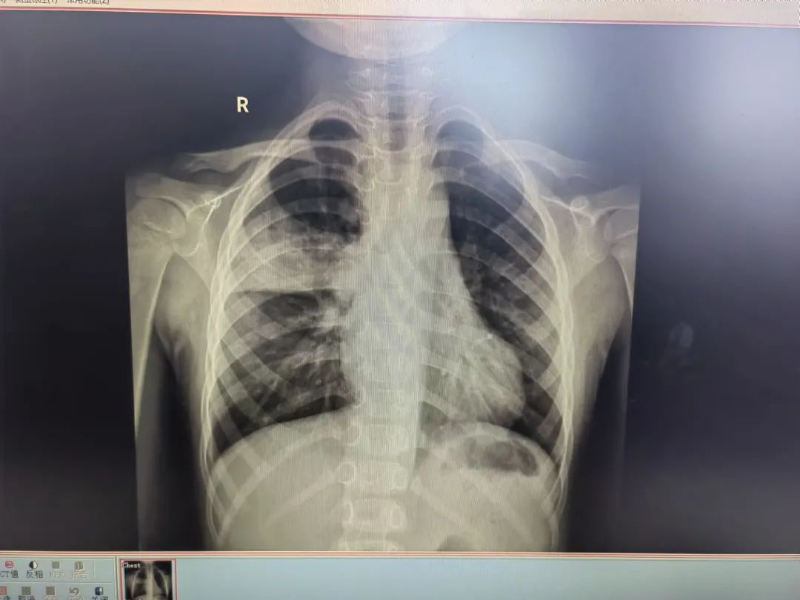

門診胸片結果顯示,帆帆的右上肺存在感染并伴有實變,結合其臨床表現,門診醫生判斷帆帆患上了兒童社區獲得性肺炎,即刻安排他入住普兒科接受治療。住院期間,普兒科副主任醫師陳玲與龍斌每天輪流多次巡房查看帆帆的病情,并耐心細致地診治。陳玲為他制定了個性化的治療方案,時刻關注其病情變化,確保治療方案的有效性和安全性。

治療前(左)、后(右)胸片對比